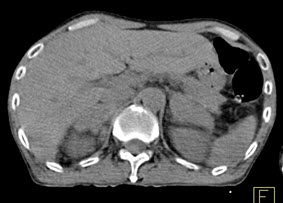

Mai Trọng Khoa và cộng sự đã tiến hành chụp 18FDG-PET/CT cho các bệnh nhân bị u lympho ác tính và nhận thấy các tế bào ác tính tại u nguyên phát và các tổ chức di căn hấp thu mạnh 18FDG và có sự chênh lệch rõ rệt hoạt độ phóng xạ của dược chất phóng xạ này so với các tổ chức xung quanh. Vì vậy 18FDG-PET/CT rất có giá trị trong chẩn đoán u nguyên phát và phát hiện các di căn của u lympho ác tính không Hodgkin với độ chính xác cao. Có thể thấy rõ hơn những nhận định trên qua các hình ảnh PET/CT của một số bệnh nhân u lympho ácc tính không Hodgkin tại Trung tâm Y học hạt nhân và Ung bướu, bệnh viện Bạch Mai.

Hình 5. Bệnh nhân Nguyễn X.T., nam, 58 tuổi. Chẩn đoán: U lympho ác tính không Hodgkin, giải phẫu bệnh: WF6. Hình PET cho thấy tổn thương ở phổi, hạch, xương, tuyến thượng thận hai bên (mũi tên). Hình CT và PET/CT cho thấy tổn thương tăng hấp thu FDG tại vị trí tuyến thượng thận hai bên (mũi tên), max SUV=11,34.

Hình 6. Bệnh nhân Vũ D.L., nam, 56 tuổi. Chẩn đoán: Non Hodgkin Lymphoma , GPB: WF7.Hình PET/CT trước và sau điều trị. Trước điều trị bệnh nhân có tổn thương hạch tại rất nhiều vị trí trong cơ thể: hạch cổ, hạch trung thất, hạch ổ bụng. Sau điều trị hóa chất 6 đợt, bệnh nhân được chụp PET/CT để đánh giá đáp ứng điều trị thấy các hạch hoàn toàn biến mất. Bệnh đáp ứng hoàn toàn.